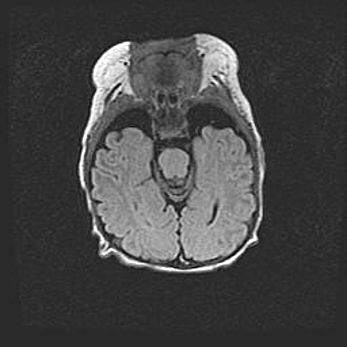

Лейкомаляция с кистозно-глиозной дегенерацией головного мозга.

Возраст: 2 месяца 25 дней

Вес: 6400 г

Окружность головы: 40 см

Срок гестации: 41 неделя

Лейкомаляцию относят к ишемически-гипоксическим повреждениям головного мозга, диагностируемым у новорожденных. При лейкомаляции в головном мозге обнаруживают очаги некроза, возникшие после тяжелой гипоксии и нарушения кровотока. В процессе морфогенеза очаги проходят три стадии: 1) развития некроза, 2) резорбции и 3) формирования глиозного рубца или кисты. Перивентрикулярная лейкомаляция (ПЛ) встречается примерно в 12% случаев среди новорожденных, обычно – у недоношенных детей, причем, частота ее зависит от массы, с которой младенец появился на свет. Наибольшее число малышей страдает лейкомаляцией, если масса при рождении 1500-2500 г.